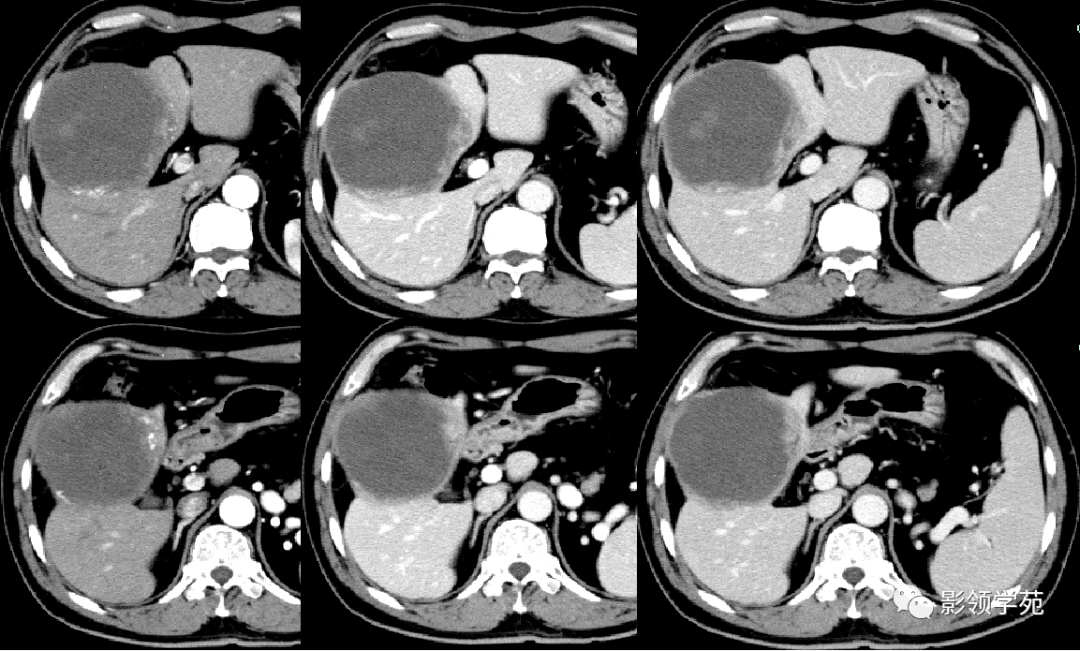

肝癌:增强ct,典型"快进快出".

图片尺寸640x480